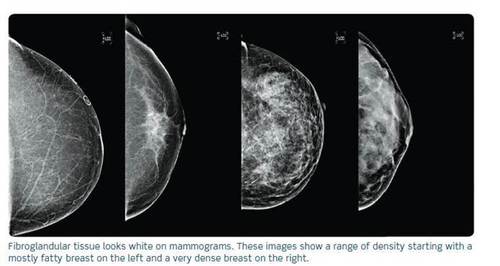

Jacobs has dense breasts and her breast tissue appears white on a mammogram, the same color as cancer.

Dense breast tissue is a common physical attribute, like freckled skin or curly hair. About four in every 10 women have it. (The percentage is even higher in Asian women.) There is no way to tell whether a woman has dense breasts without a mammogram, and density can be a factor regardless of age or breast size.

Although women with dense breasts may have a four to six times higher risk of breast cancer, the real danger is the dense tissue’s ability to obscure cancers on a mammogram. “It’s literally like looking for a snowball in snowstorm,” says Dr. Jessie Jacob, chief medical officer for breast health at GE Healthcare.

Jacob says that mammography, which uses a low-dose of X-rays to image breasts, is still the gold standard in breast cancer screening. But for women with dense breast tissue, a clinician may not see everything with a mammogram alone. That’s because dense breasts contain more “glandular elements” than fatty tissue. “The fatty tissue lets you see through, but the glandular elements can obscure masses,” Dr. Jacob says.